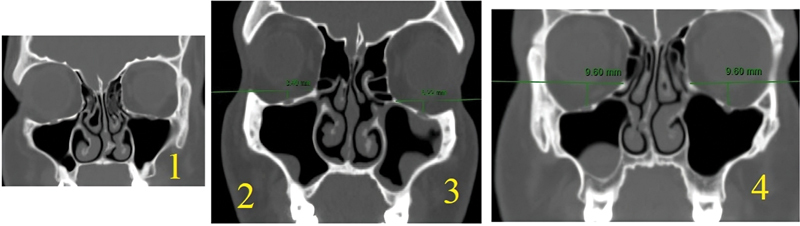

Introduction  The preoperative assessment of the computed tomography (CT) characteristics of the maxillary sinus helps to preserve its anatomical and functional integrity during and after surgery. Objective  To use CT scanning to identify maxillary sinus variations and types that were not previously published. Methods  The present study was carried out on 110 paranasal CT scans (220 sides). Axial images were obtained with multiplanar scans, to visualize details in coronal and sagittal planes for all subjects. Results  Among the 110 CTs (220 sides) of the maxillary sinus's floor, there were 53.2% type 1, 29.1% type 2, 10% type 3, and 7.7% type 4, with significant difference between genders. The most common maxillary sinus floor was type 1. The lateral maxillary sinus wall was found to be type 1 in 32.7%, type 2 in 65%, and type 3 in 2.3%, with a significant difference between genders. The most common lateral wall of the maxillary sinus type was type 2. The orbital floor was found to be type 1 in 0.9%, type 2 in 21.3%, type 3 in 50.5%, and type 4 in 27.3%, without significant difference between genders. Asymmetry was detected between the right and left sides for the maxillary sinus floor of in 22.7%, lateral maxillary wall in 16%, and orbital floor (maxillary roof) in 30%. Conclusion  This study aims to increase surgeons' awareness of maxillary sinus variations, creating new classifications for usage and communication in the otorhinolaryngology and endoscopic fields. It could also be helpful for training medical residents.

Abstract Image